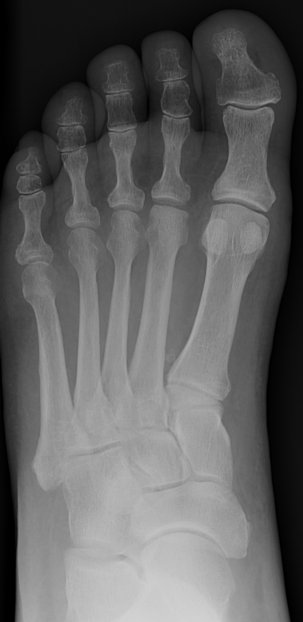

Return to Freiberg's Infarction